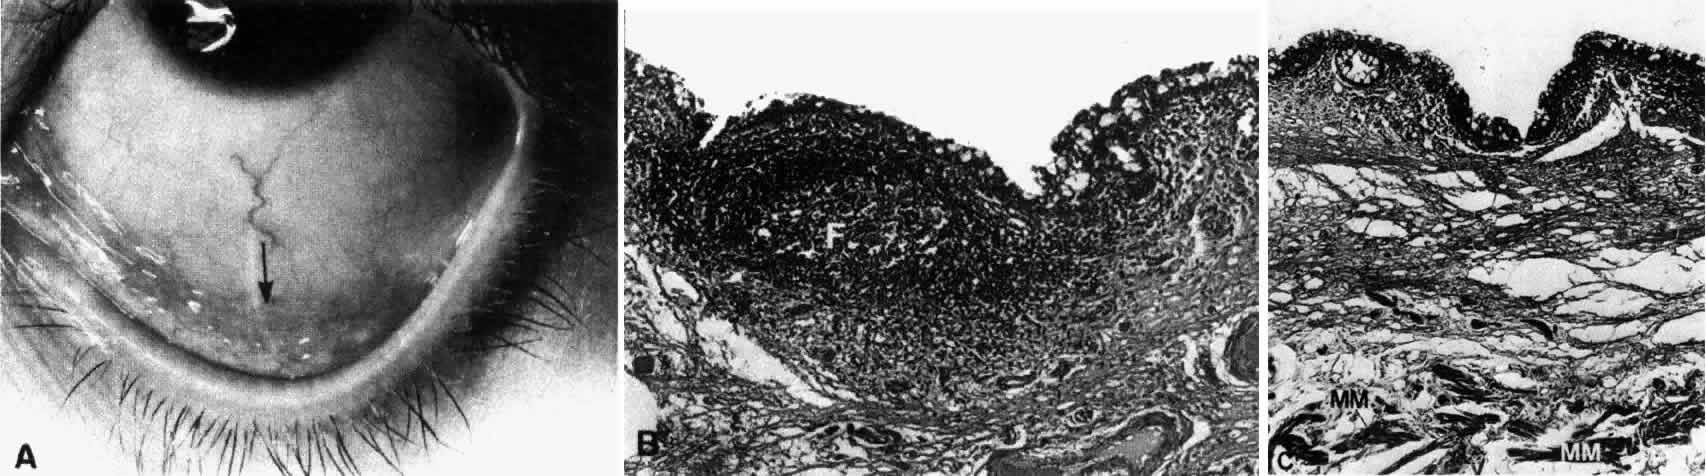

The conjunctiva lines the posterior surface of the upper and lower lids and the anterior surface of the globe. From the inner surface of the lid it is reflected forward onto the globe above and below, forming two recesses: the superior and inferior fornix. The superior fornix is located at the level of the orbital margin 8 to 10 mm from the limbus (Fig. 1A, B, and C). The inferior fornix is approximately 8 mm from the limbus (Fig. 2A, B, and C). On the medial side, the forniceal structures are replaced by the caruncle and the plica semilunaris (Fig. 3). The absence of the fornix on the medial side is necessary in order to allow the inferior punctum to dip and drain from the superficial tear fluid layer.10 Laterally, the fornix extends just behind the equator of the globe (Fig. 4). It is quite deep and approximately 14 mm from the limbus.

Fig. 1. Low-power view of the globe. A. Arrow pointing to the region of the superior fornix. B. Superior fornix (F) showing epithelium and substantia propria. Conjunctival sac (CS). C. Higher-power view of epithelium showing goblet cells on the surface (arrows). (B, × 50; C, × 170)

Fig. 2. A. Region of the inferior fornix (arrow). B. Inferior fornix showing epithelium, goblet cells, and a follicle (F). C. Inferior fornix showing Müller's muscle (MM) in the substantia propria. (B, × 60; C, × 80)